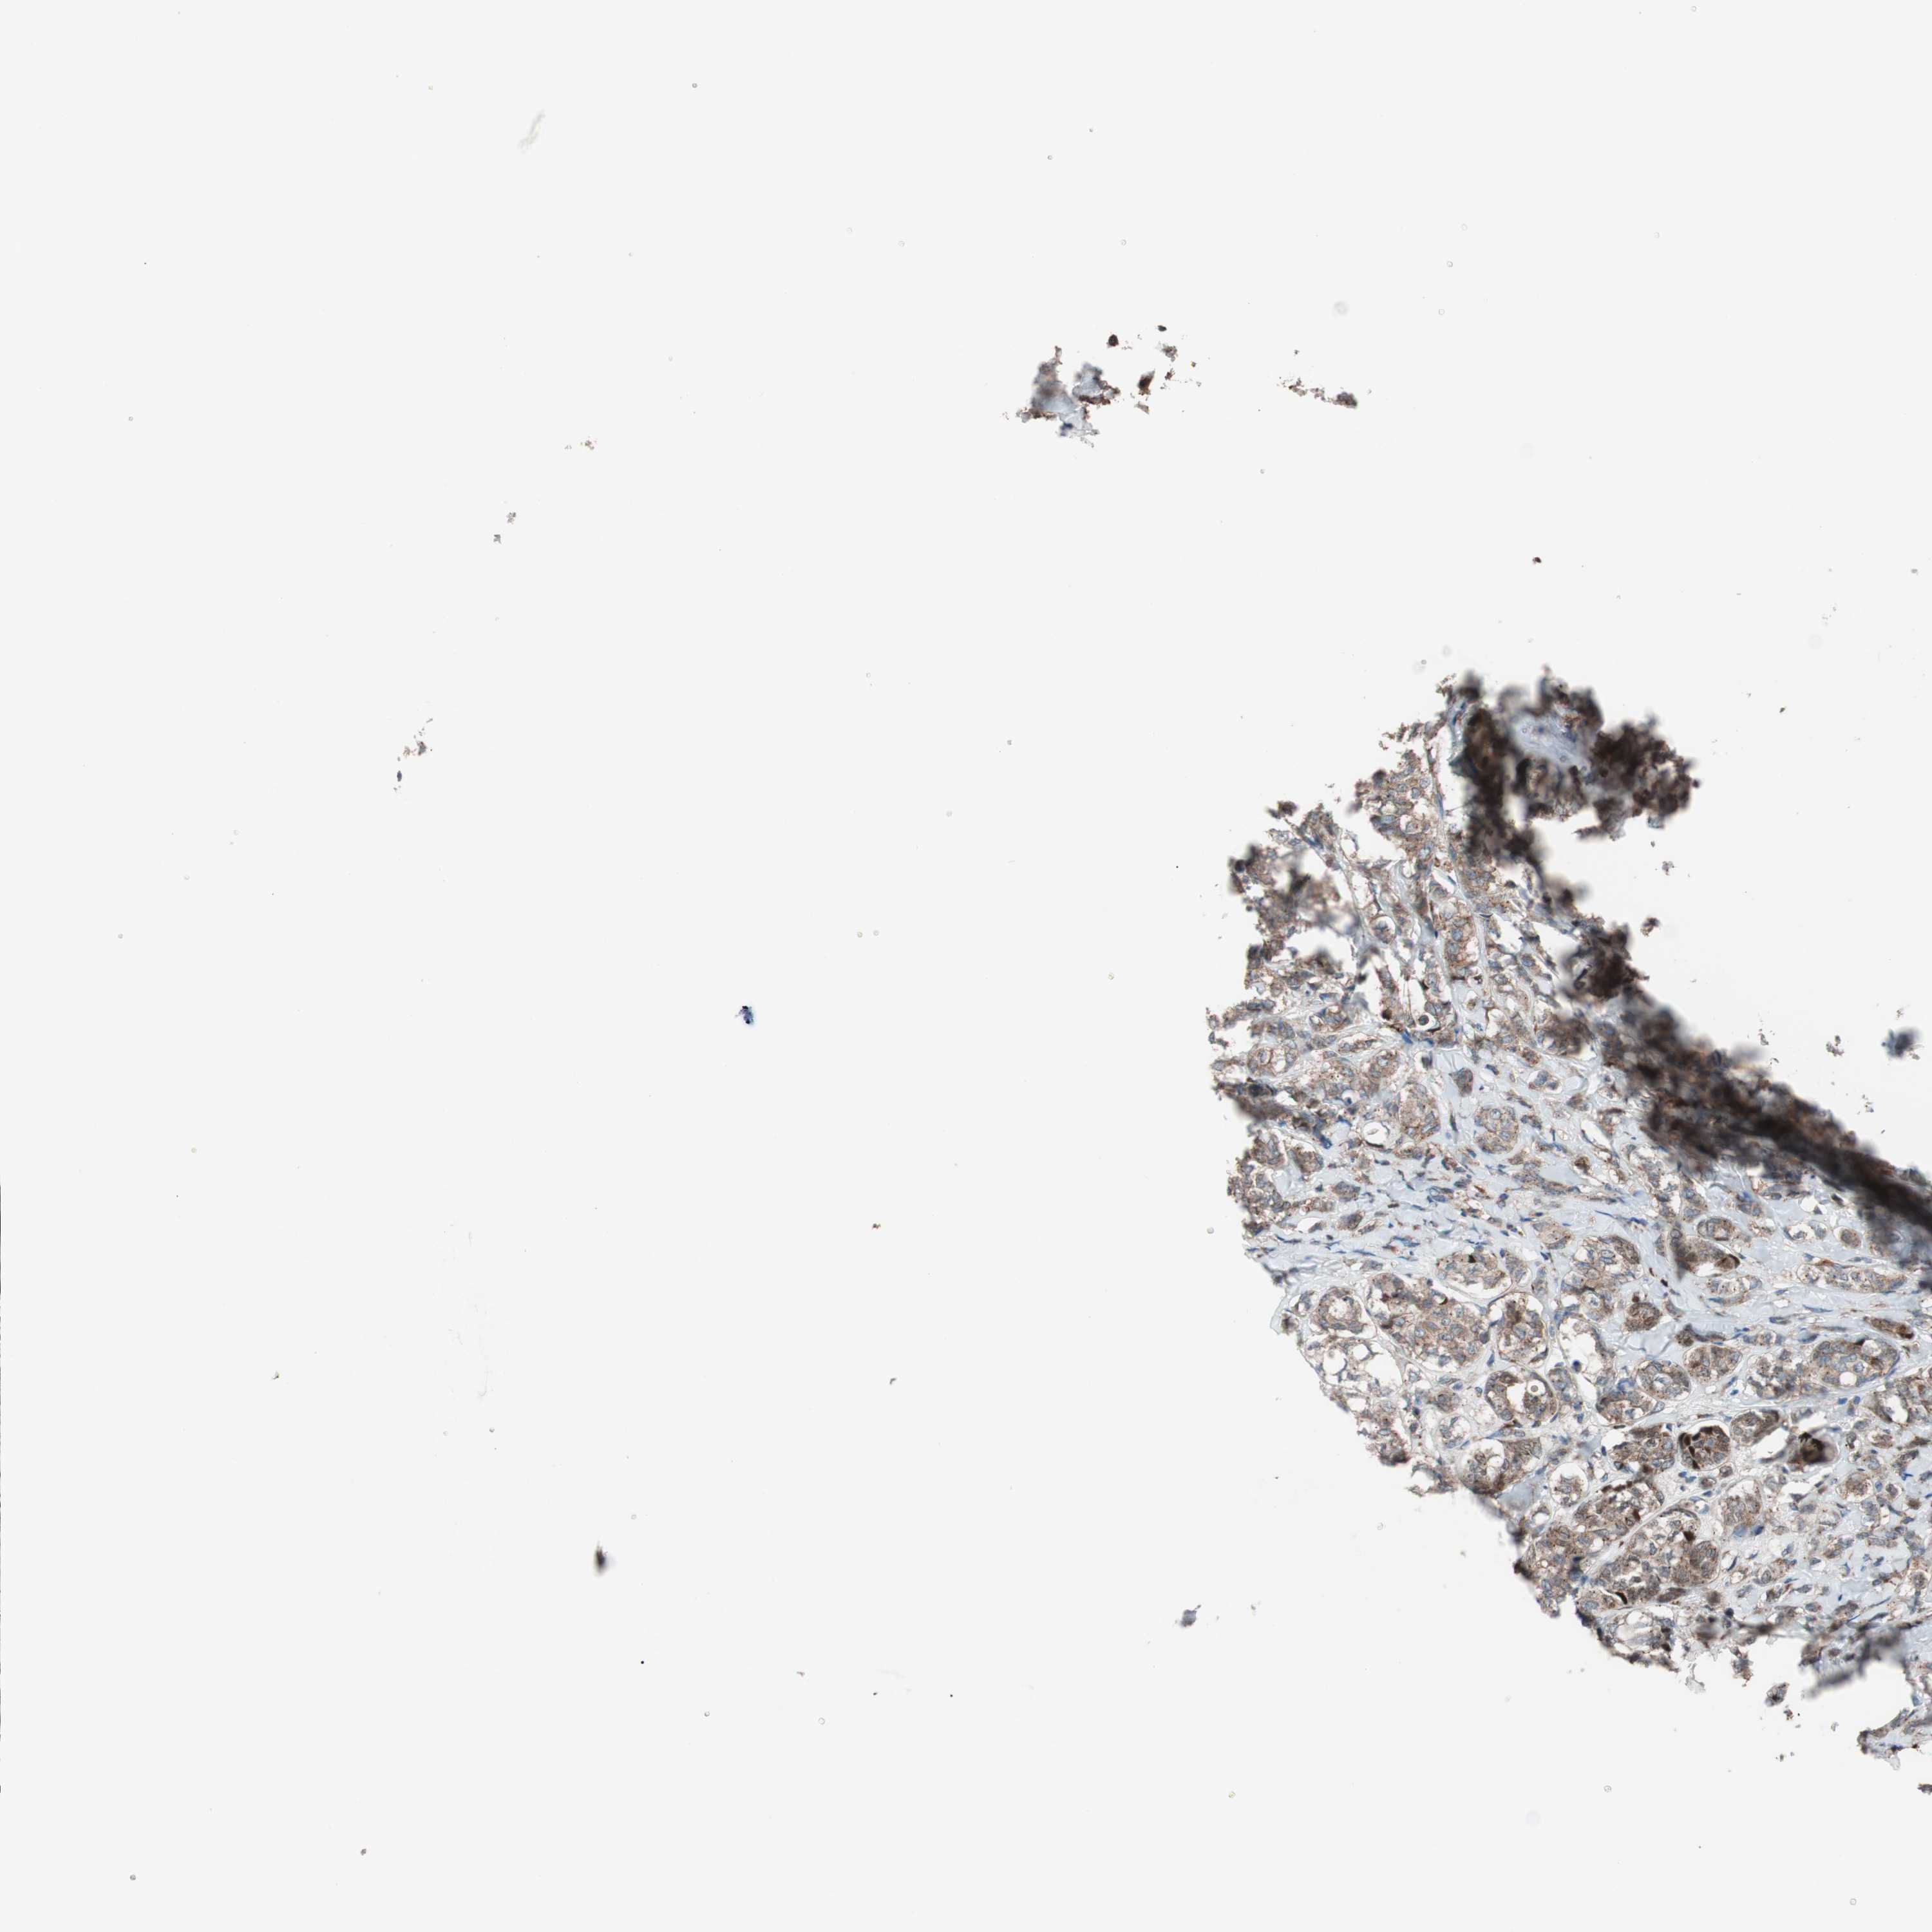

CANCER BREAST CANCER Show tissue menu

BRCA TCGA BRCA VALIDATION PROTEIN EXPRESSION